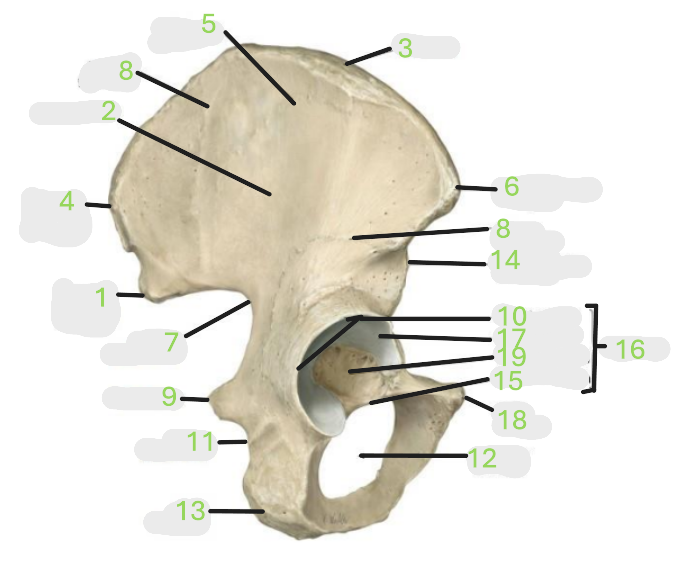

Where is the posterior inferior iliac spine

1

Where is the gluteal surface

2

Where is the iliac crest

3

Where is the posterior superior iliac spine

4

Where is the anterior gluteal line

5

Where is the anterior superior iliac spine

6

Where is the greater sciatic notch

7

Where is the inferior gluteal line

8

Where is the ischial spine

9

Where is the acetabular rim

10

Where is the lesser sciatic notch

11

Where is the obturator foramen

12

Where is the ischial tuberosity

13

Where is the anterior inferior iliac spine

14

Where is the acetabular notch

15

Where is the acetabulum

16

Where is the lunate surface

17

Where is the pubic tubercle

18

Where is the acetabular fossa

19